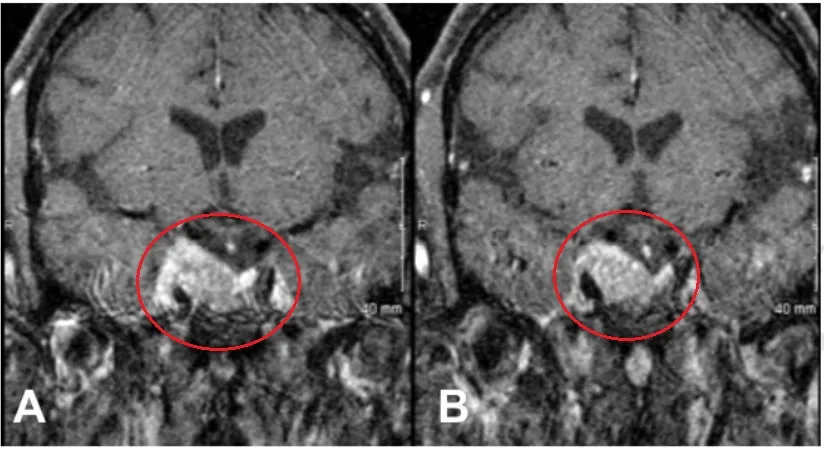

▼术前影像显示肿瘤持续生长并侵入海绵窦

术中通过超声检查定位内眦动脉,暴露其内侧及鞍外侧的硬脑膜,以进入内侧通道。质地柔软的复发肿瘤被成功移除。

海绵窦段的颈内动脉清晰可见,肿瘤已发生骨质化。海绵窦的内侧壁被暴露,镜下观察显示其完整,与鞍区无明显联系;对鞍区中线进行探查,未见肿瘤组织。动眼神经沿颈内动脉向后下方走行的路径清晰可见。

术后磁共振成像证实肿瘤实现大体全切除。

▼术后磁共振显示患者动眼神经麻痹症状消退,影像学随访至少3年未见肿瘤复发或进展。